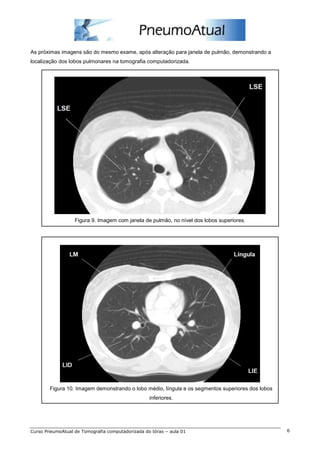

As próximas imagens são do mesmo exame, após alteração para janela de pulmão, demonstrando a

localização dos lobos pulmonares na tomografia computadorizada.

Figura 9. Imagem com janela de pulmão, no nível dos lobos superiores.

Figura 10. Imagem demonstrando o lobo médio, língula e os segmentos superiores dos lobos

inferiores.